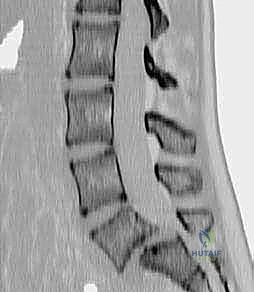

- التصوير بالرنين المغناطيسي (MRI): هو المعيار الذهبي لرؤية الأنسجة الرخوة. يوضح بدقة متناهية حالة الأقراص الغضروفية، ومقدار الاختناق في القناة الشوكية، والضغط الواقع على جذور الأعصاب.

- التصوير المقطعي المحوسب (CT Scan): يقدم تفاصيل دقيقة للبنية العظمية، وهو ضروري جداً للتخطيط الجراحي وتحديد مسار المسامير (Pedicle Screws) في الجراحة.

3. دمج الفقرات بين الأجسام الفقرية (PLIF / TLIF)

في حالات الانزلاق عالي الدرجة، غالباً ما يتطلب الأمر دعماً إضافياً من الأمام (بين أجسام الفقرات). هنا يتألق الدكتور هطيف باستخدام تقنيات (PLIF - Posterior Lumbar Interbody Fusion) أو (TLIF - Transforaminal Lumbar Interbody Fusion).

في هذه التقنية، يتم استئصال القرص الغضروفي التالف بالكامل، ووضع قفص داعم (Cage) مصنوع من مادة الـ PEEK أو التيتانيوم، ومملوء بالطعوم العظمية، في مكان الغضروف. هذا الإجراء يعيد الارتفاع الطبيعي للفقرات، ويفتح مسارات الأعصاب بشكل ممتاز، ويوفر نسبة نجاح للدمج العظمي تقارب 100% لأنه يضع العظم في منطقة تتحمل ضغطاً ميكانيكياً عالياً مما يحفز نمو العظام.